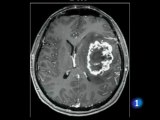

La neurocisticercosis es una enfermedad del sistema nervioso central de origen parasitario que genera una alta morbilidad. Es causada por el cisticerco del cerdo. Puede ser asintomática y tiene buen pronóstico si es tratada a tiempo. Ocasiona sobre todo epilepsia crónica. Es endémica en muchas regiones del mundo, principalmente en países en vías de desarrollo. Es causada por la ingestión de huevos de Taenia solium, cuya vía es fecal-oral, de una persona con teniasis a una persona sana.